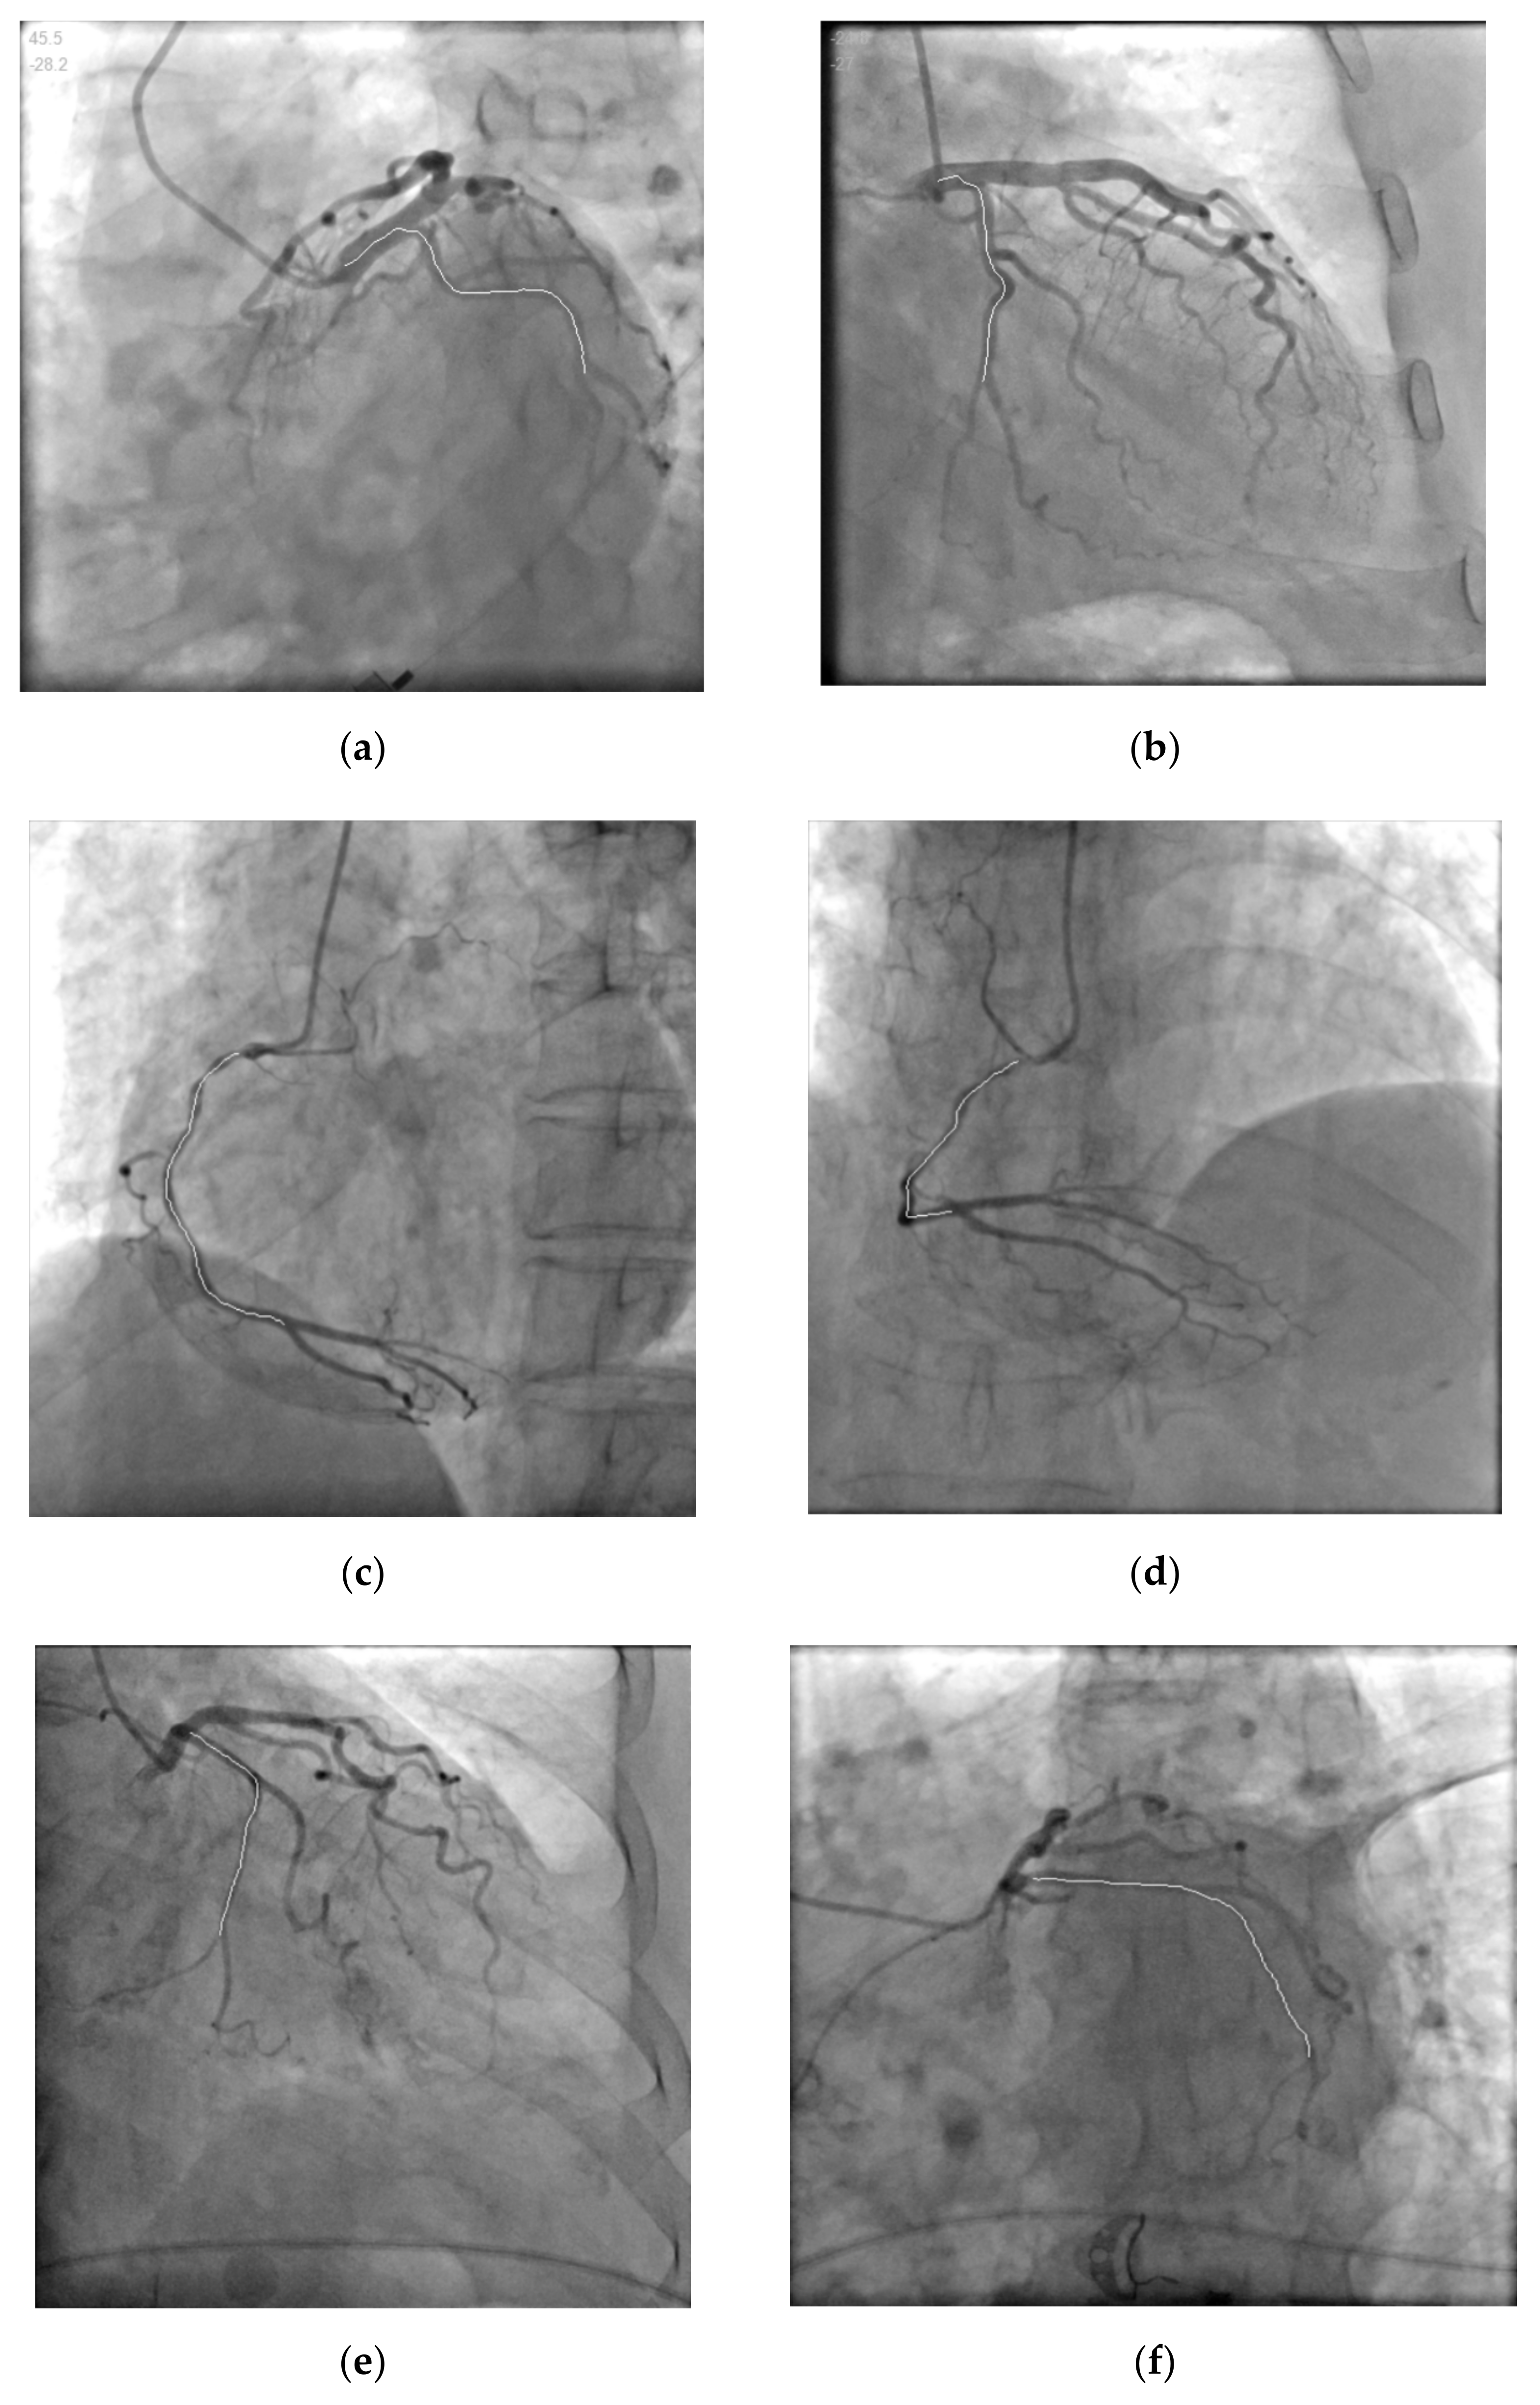

| Data.2 | (c) | 45.2 | 0 | 1028 | 759.4 |

| (d) | 0.9 | 33 | 1064 | 766.4 | |

| Data.3 | (e) | −21.6 | −21 | 1075 | 782.7 |

| (f) | 44.3 | −28.8 | 1118 | 785 |